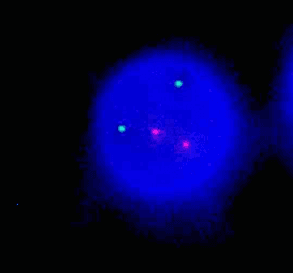

1p32/1q21 dual color probe(1q21 green、1p32 orange)

1p32 (CDKN2C) labeled as orange, with a length of 210 kb; 1q21 (CKS1B) labeled as green, with a length of 356 kb.